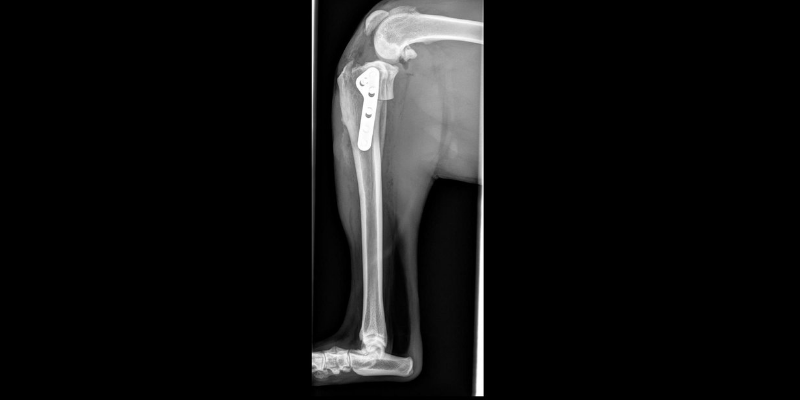

5. Fracture Repair

We often see dogs and cats with broken bones, especially in the warmer months. Fractures can occur at any age and happen after trauma such as being hit by a car or landing awkwardly while playing or jumping. The most common repair is with a plate and screws. How the fracture is repaired depends on where it is (what bone and what part of the bone) and in how many pieces.

Surgery recovery usually requires 8-12 weeks of activity restriction. Recheck x-rays are performed between 4-8 weeks post-surgery to evaluate healing before allowing the pet to return to normal activity.